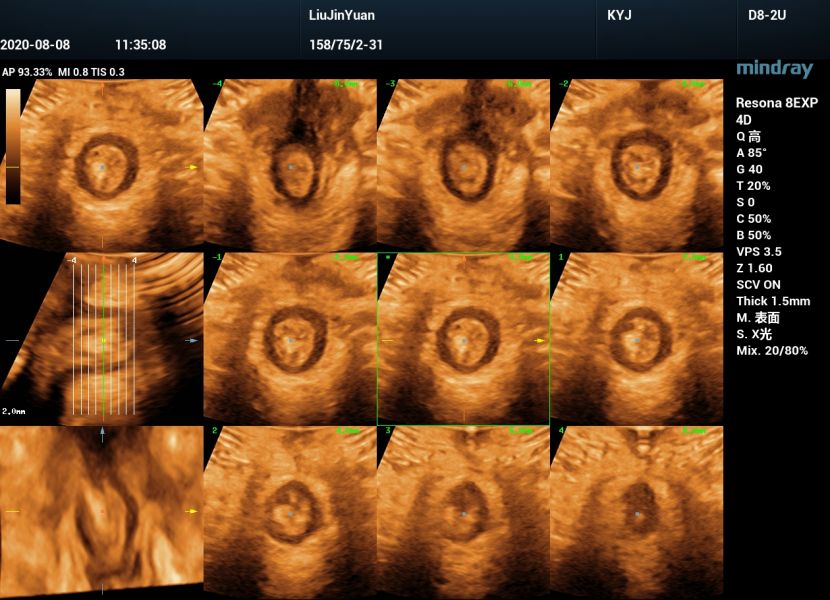

肛门括约肌四维图片